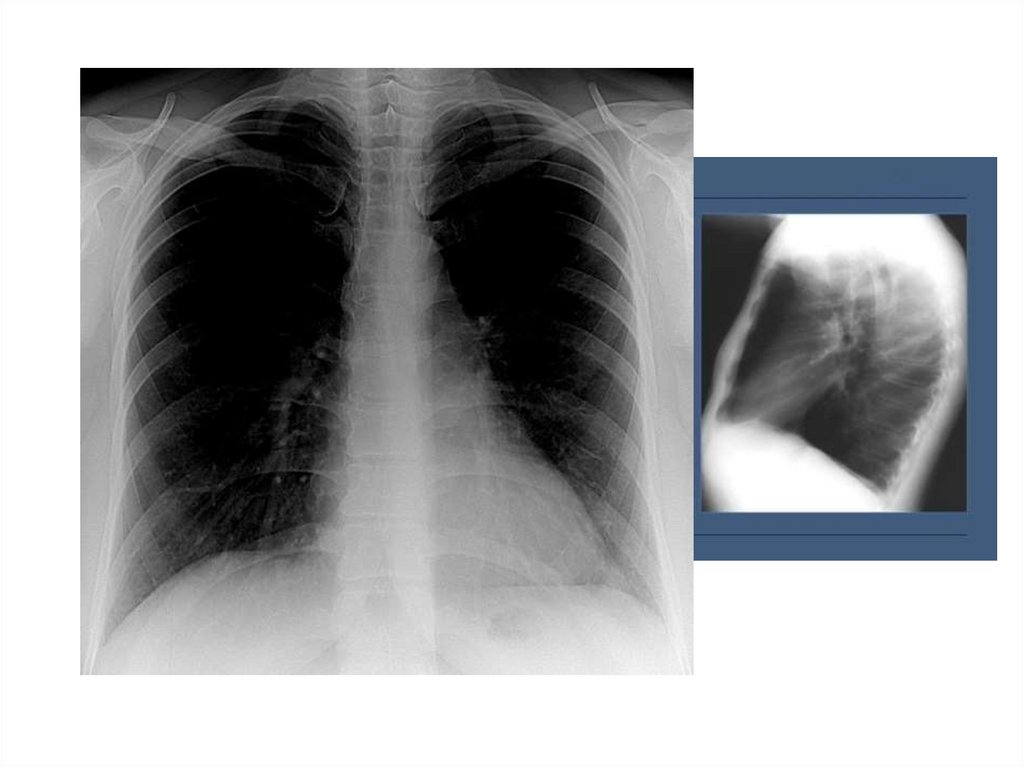

21. Обструкция бронха

Или обтурационная эмфизема, которая

развивается в результате бронхиальной астмы,

пневмонии, бронхита, бронхиолита,

пневмосклероза.

Видимая картина – тотальное одностороннее

просветление пораженного легкого.